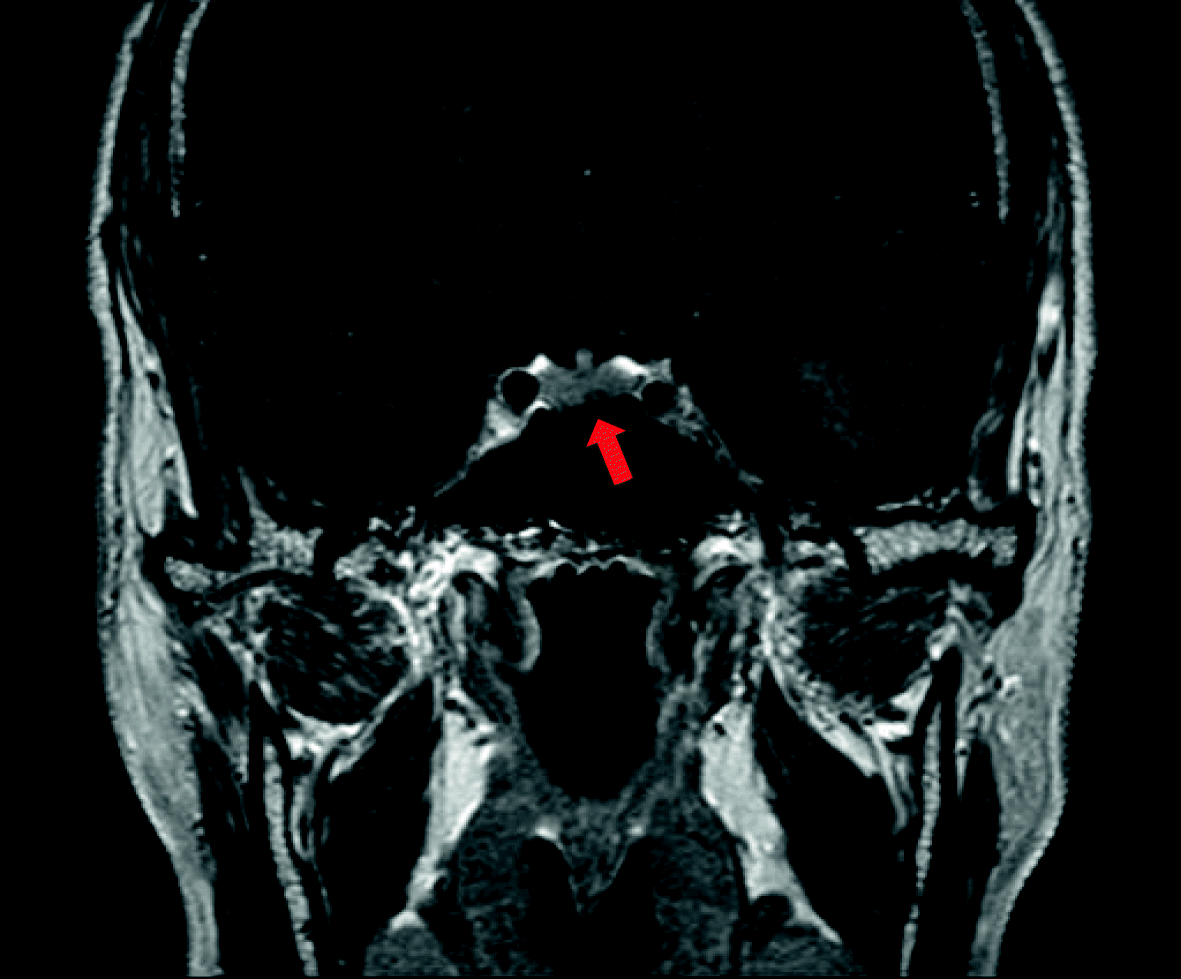

Fig. 5From: A rare case of multiple endocrine neoplasia type 1 initially presenting as an asymptomatic, huge mediastinal mass: case reportSella MRI (coronal T1-weighted postcontrast) showing a 0.3-cm-sized, delayed enhancing lesion of the pituitary gland, suggestive of a pituitary microadenoma (red arrow)Back to article page